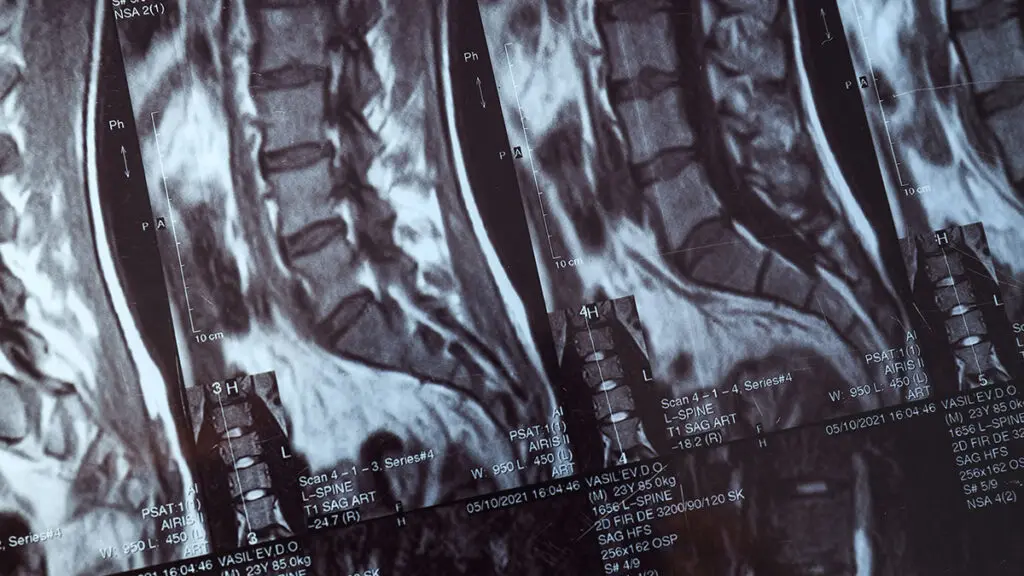

Una visita specialista schiena presso Global Spine Solutions è il primo passo per ricevere una diagnosi accurata e un piano terapeutico personalizzato per la tua patologia vertebrale. Durante la visita, il neurochirurgo analizza la sintomatologia, esamina gli eventuali esami diagnostici disponibili (RMN, TAC, radiografie) e valuta le opzioni di trattamento più appropriate.